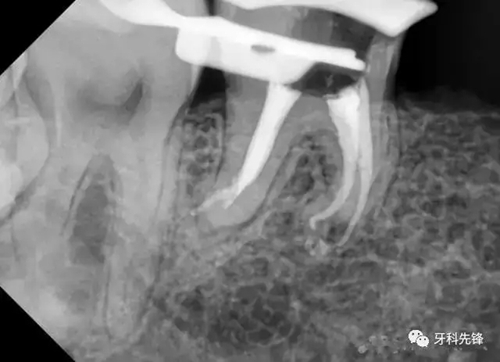

處置: 46右下牙槽神經(jīng)阻滯麻醉,46橡皮障隔濕,去凈腐質(zhì),開髓,拔髓,GG鉆擴(kuò)大根管口,根管疏通,根測,ML=19.5mm,MB=18mm,DB=DL=18mm,EDTA作用下M2鎳鈦機(jī)擴(kuò)至25#,試尖拍片,干燥根管,AHplus糊劑+牙塞尖+熱牙膠加壓根充,,聚羧酸鋅墊底,Z350納米樹脂充填,調(diào)合,拋光。

如果沒有橡皮障和MTwo,很難完成這個(gè)病例。